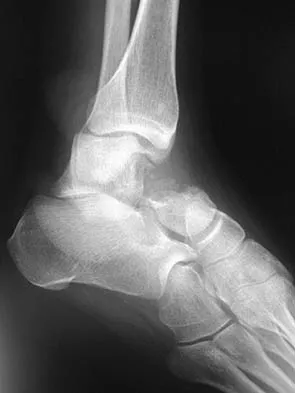

A 16-year-old snowboarder has significant pain and is still unable to bear weight after sustaining a lateral ankle injury in a fall 1 week ago. Examination reveals swelling and tenderness in the sinus tarsi. AP, lateral, and mortise radiographs of the ankle are unremarkable. Management should consist of

Explanation

Because there is a significant possibility that the patient may have a fracture of the lateral process of the talus, there is some disagreement as to the best radiographic study to identify this injury. A CT scan is an appropriate diagnostic tool to visualize the fracture and identify any displacement. Displaced lateral process fractures are best treated surgically. Kirkpatrick DP, Hunter RE, Janes PC, Mastrangelo J, Nicholas RA: The snowboarder's foot and ankle. Am J Sports Med 1998;26:271-277.